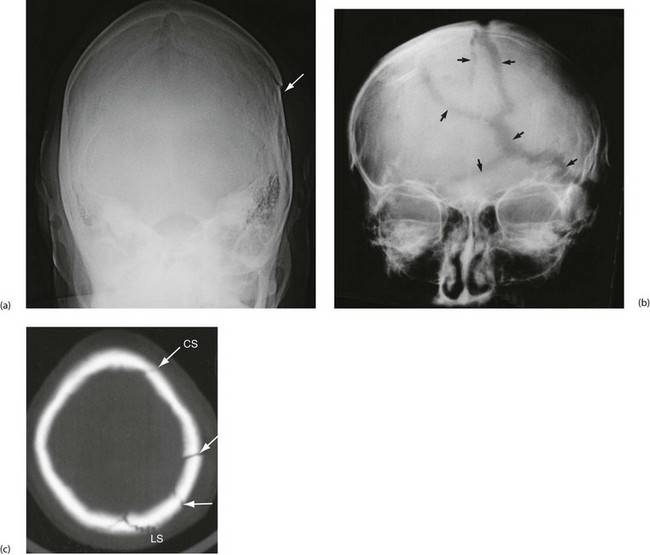

Extradural (epidural) haemorrhage: Extradural haemorrhage occurs when blood accumulates in the space between dura and calvarium. It is most common in children and younger adults, because their dura is less adherent to the skull. Most have a skull fracture, usually in the temporal region (Fig. 16.5). Almost 90% are due to rupture of an artery, usually the middle meningeal or a branch. Immediately after injury causing loss of consciousness, in up to half the patients, there will be a lucid interval, perhaps with no symptoms other than worsening headache. In either group, this is followed by deteriorating conscious level; temporal lobe herniation then leads to compression of the third nerve and pupillary dilatation. Death quickly follows unless the haematoma is evacuated rapidly. Emergency CT scanning is indicated to confirm the diagnosis (typically a lentiform-shaped clot—see Fig. 16.5b) and to show its position. With increased awareness of the condition and widespread availability of CT scanning, emergency ‘blind’ burr hole drainage is almost never appropriate. Urgent transfer to a neurosurgeon for craniotomy is the best course of action, almost without exception.

Subdural haematoma: Subdural haematoma usually results from tearing of veins passing between cerebral cortex and dura, or from injury to vessels on the surface of the brain. Blood accumulates in the large potential space between dura mater and arachnoid mater. The haematoma tends to spread laterally over a wide area (Fig. 16.6). In contrast to extradural haemorrhage, there is usually underlying primary brain injury. Acute subdural haemorrhage is more common in older adults because the brain is more mobile within the cranial cavity.

Post-traumatic intracranial bleeding is classified into extradural (epidural), subdural, intracerebral or subarachnoid (see Fig. 16.4). Intracranial bleeding acts as a mass lesion causing a general rise in ICP, whilst local brain compression can cause focal neurological deficit. Untreated, raised ICP may cause ‘coning’. One or both temporal lobes herniate through the tentorium cerebelli, compressing the third nerve and midbrain, whilst herniation of the cerebellar tonsils through the foramen magnum compresses the medulla, causing neurological deterioration and often death. Rising intracranial pressure manifests initially with deteriorating conscious level. Late clinical signs are: